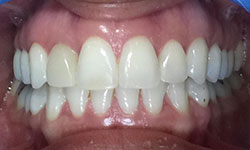

(9) Metal Ceramic Crowns

Before Treatment

After Treatment

Mr. Shiv Narayan Singh,aged 78yrs, came with a concern of multiple broken and mobile teeth with difficulty in chewing food. So, multiple RCTs followed by metal-ceramic crowns were delivered to the patient ,restoring his beautiful smile.